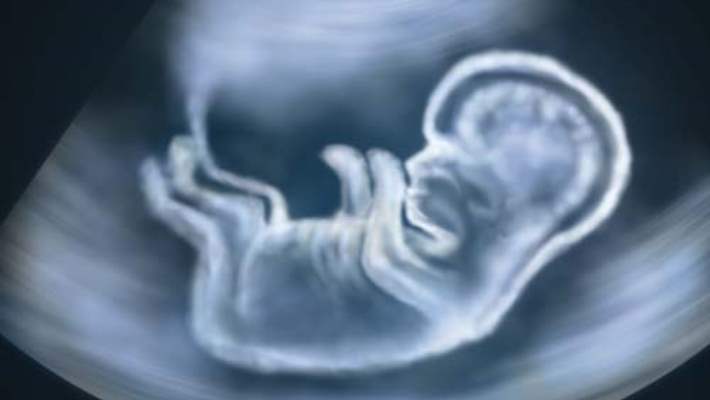

Gebeliğin 9. haftası, yani 8+0 ila 8+6 günler arasında bebek hızla büyümeye devam edecektir. Bu haftanın sonuna doğru bazen ultrasonda bebeğin hareketlerini görmek de mümkün olabilecektir. Ultrasonda, başının ve gövdesinin büyüklüğünün aynı olduğu görülür. Bu normaldir. Çünkü embriyolarda, yönetim organı olduğu için beyin hızlı gelişir. Bu yüzden kafatası en büyük organlardan biridir. Ancak bir süre sonra, organlar normal hallerine döneceklerdir. Yine ultrasonda, kolların ve bacakların çok kısa olduğu gözlemlenecektir. Bu da son derece normaldir. Çünkü kollar ve bacaklar ilk gelişmeye başladıklarında, vücuda göre oldukça kısadırlar. Ama 12-13. haftalarda hem başın hem de kolların ve bacakların büyüklüğü normal haline ulaşacaktır. Yine duyulan kalp atışlarının çok hızlı olması da normaldir. Çünkü, rahim içinde oksijen dış ortama göre daha az olduğundan, çok daha kısa sürede çok daha fazla oksijen taşıyabilmek için bebeğin kalp hızının yüksek olması gerekir. Bebek doğduktan sonraki saatlere kadar sürecek olan 120-160 arasında bir kalp atım sayısına sahiptir.